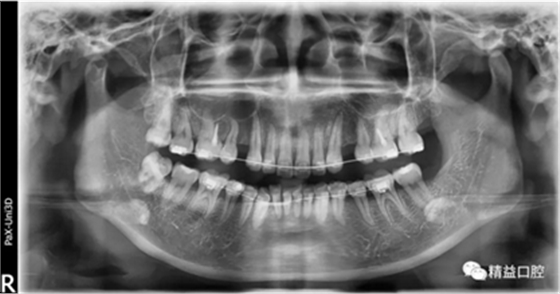

矯正前頭顱側(cè)位片

嘴唇突度非常明顯,后期經(jīng)過測量,發(fā)現(xiàn)是典型的安氏II類加骨性II類,齙牙前突。